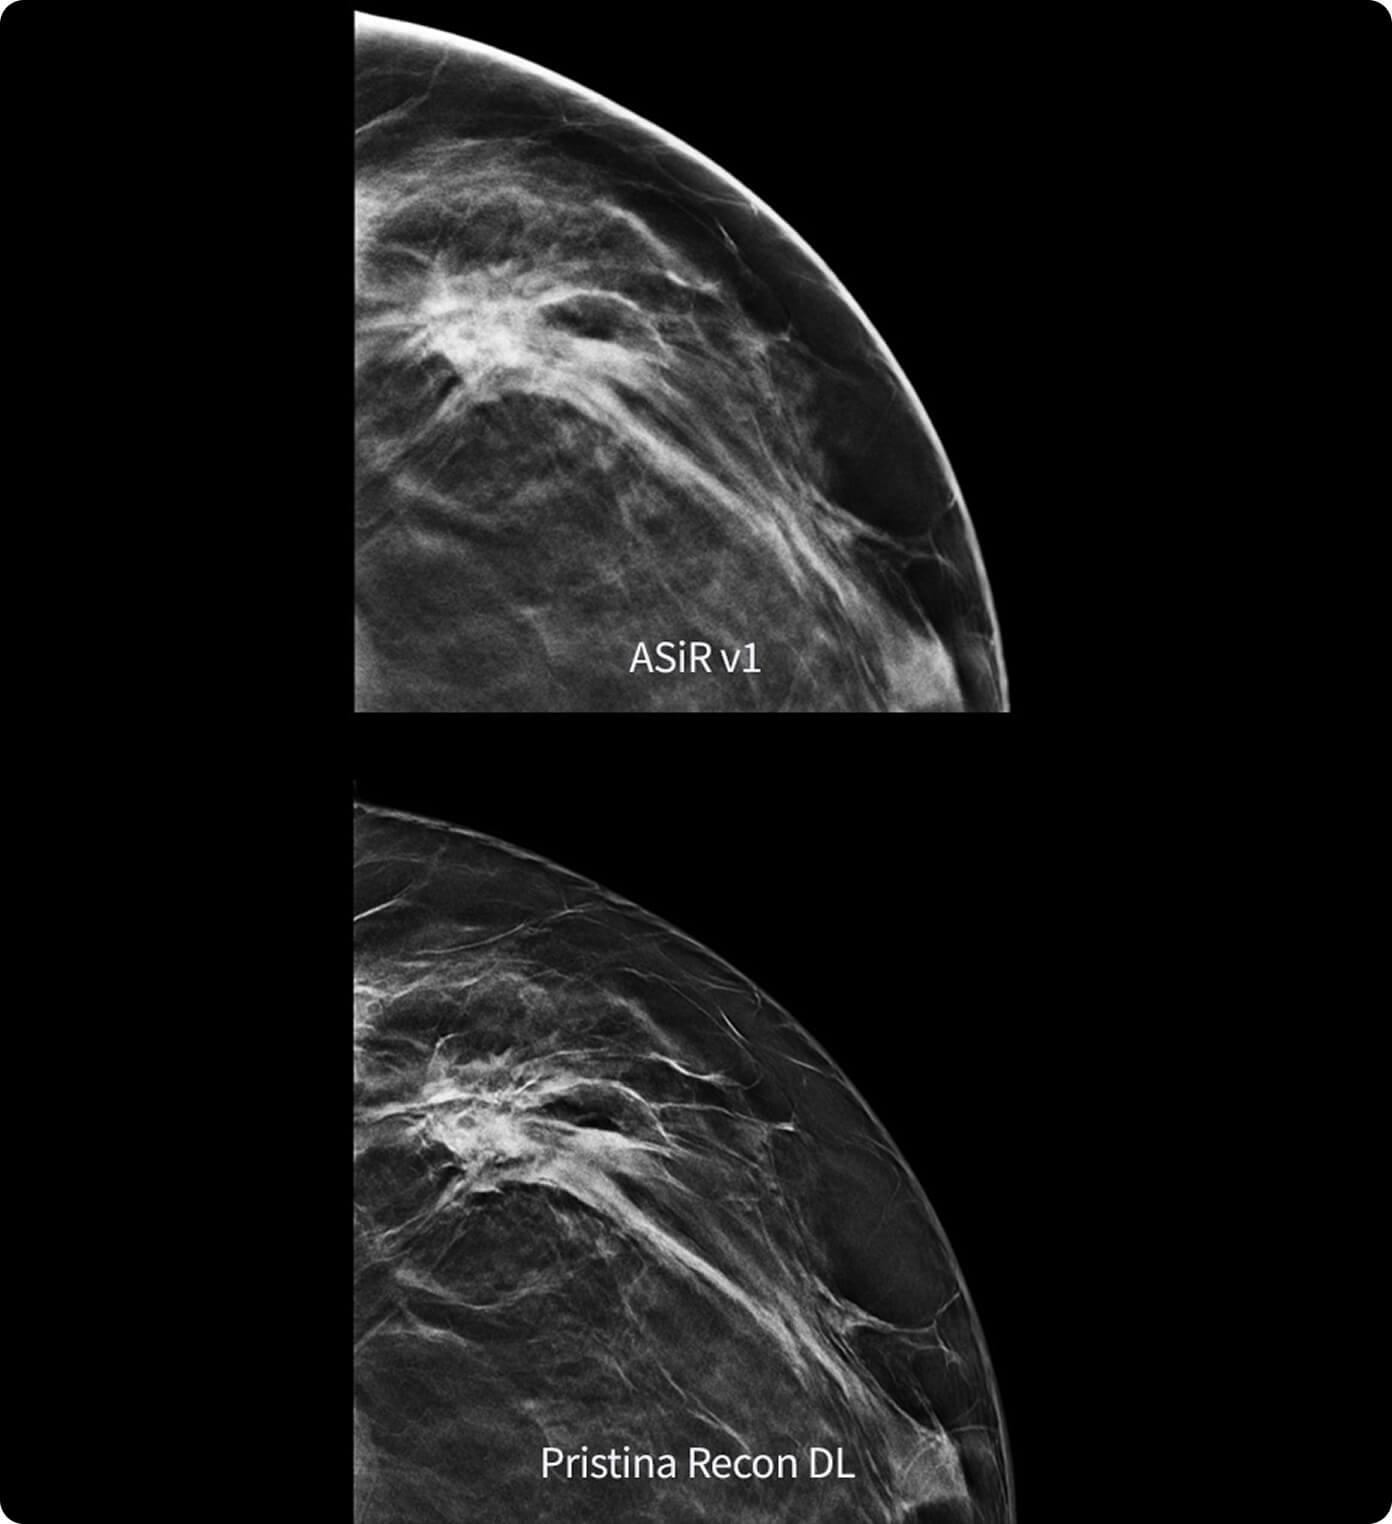

В видеоролике представлен практический опыт внедрения технологии Air Recon DL (ARDL) — технологии реконструкции МР-изображений на основе алгоритмов глубокого обучения. В отличие от традиционных методов постобработки ARDL позволяет значительно снизить уровень шума, повысить пространственное разрешение и четкость изображений без увеличения времени сканирования.